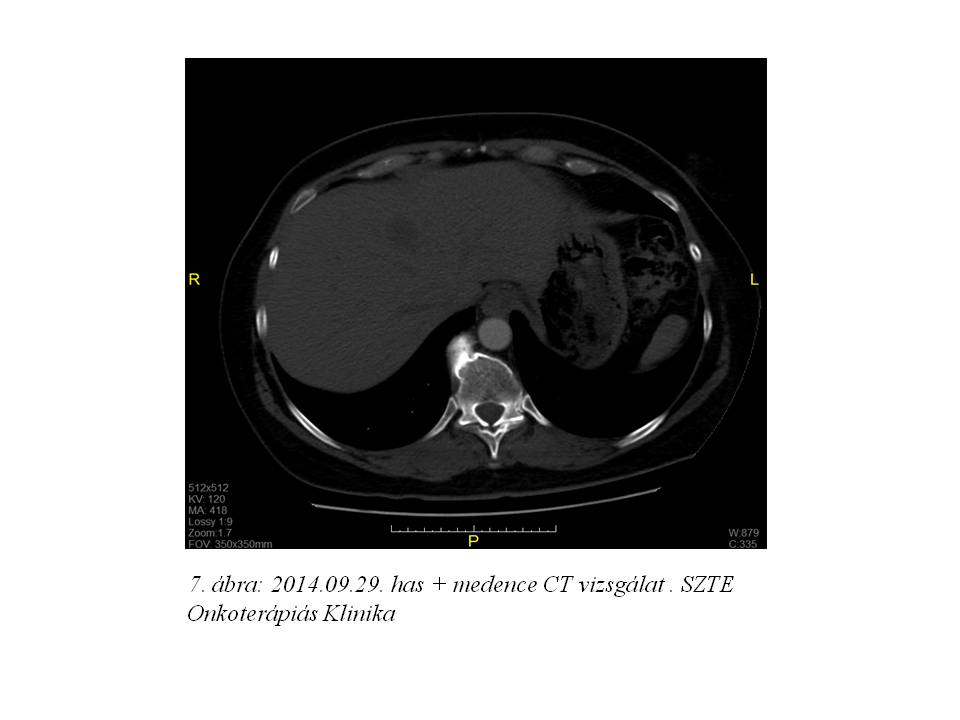

Folyamatosan emelkedő vesefunkciós paraméterek miatt azonban a palliatív kezelést nem tudtuk megkezdeni, nephrostoma beültetésére került sor. 2014. szeptemberben elvégzett friss has + medence CT mind a hepatikus metasztázisok, mind a vesepangás és a kismedencei recidíva rapid progresszióját igazolta (5. ábra, 6. ábra, 7. ábra). Mivel a vesefunkciós értékei későbbiekben sem engedték kemoterápiás kezelés indítását, szupportív terápia indult.